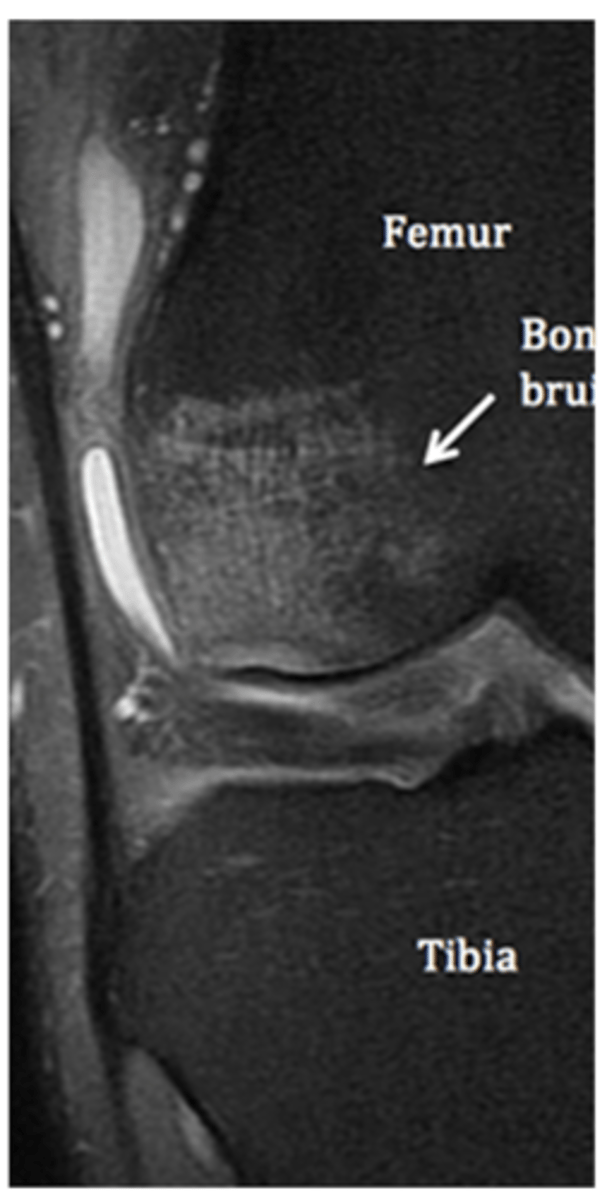

Bone edema/bone bruise

Define the pathology.